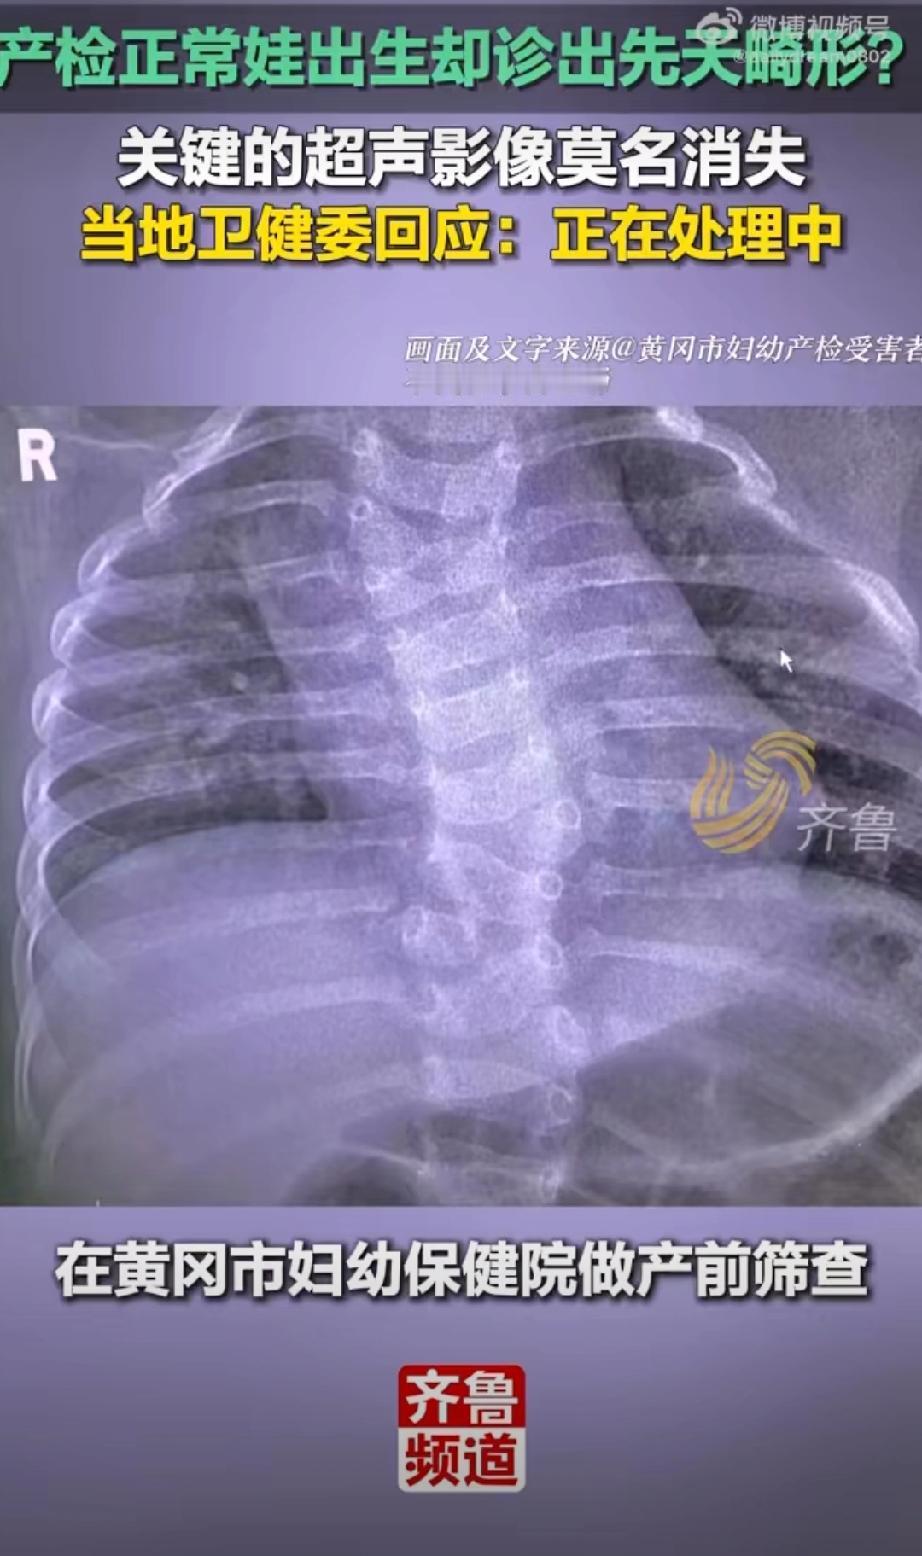

产检正常孩子却先天畸形,官方通报了,三个问题直指核心,但评论区有些气人: 1. 医生无资质:操作医生李某虽有《医师执业证》,但未取得产前筛查相关的《母婴保健技术考核合格证》,属于违规执业; 2. 操作不规范:未按国家指南要求拍摄脊柱全段关键切面,直接导致畸形漏诊; 3. 影像资料缺失:畸形最严重的颈胸段超声影像未留存,严重违反诊疗规范。 涉事人员已被处理:分管副院长被立案调查,超声科主任被免职,涉事医生被警告并调离岗位。 这个代价太过沉重了,再多的处罚与赔偿,都换不回健康孩子。愿严查医疗漏洞、严守执业规范,让所有家庭都能迎来平安健康的新生命产检诊断 胎儿畸形筛查 儿童畸形